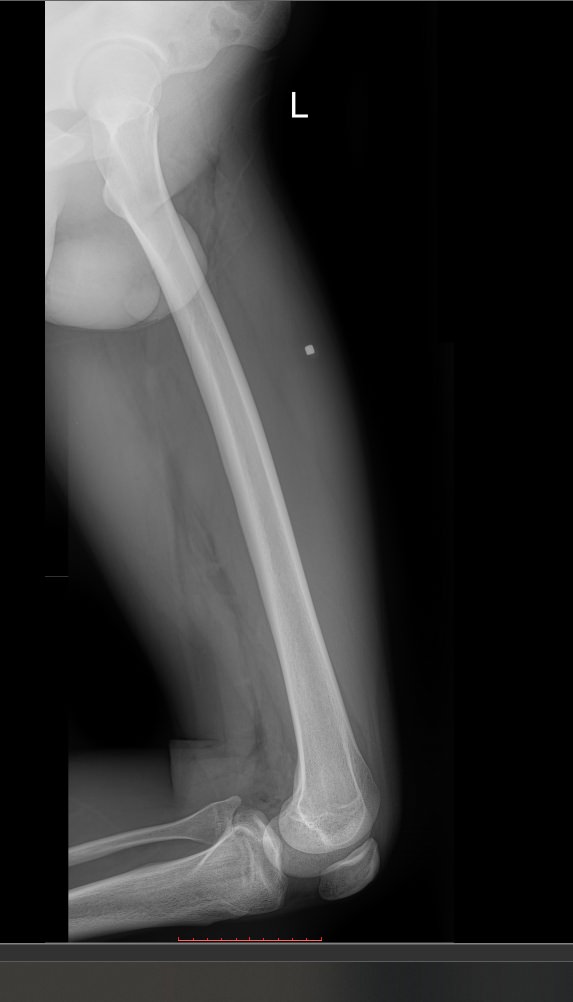

Обследование бедренной кости чаще всего выполняют рентгеновским методом. Это неинвазивный, безболезненный, высокоинформативный и доступный способ получения информации о состоянии и структуре костной ткани. Проходя через тело, рентгеновское излучение больше всего задерживается в самых плотных образования – костных, поэтому на классическом негативном снимке их изображения самые светлые. Патологические изменения, развивающихся здесь, также ясно видны. При их выявлении врач принимает решение о дополнительных видах диагностики и выбирает способы лечения.

• Состояние костной ткани и надкостницы: участки гнойного воспаления, разрежения, размягчения, деструкции, склерозирования, развития опухоли и кистозных образований;

• Изменения в мягких тканях: обызвествление, воспаление, опухоль;

• Целостность кости: свежие переломы, костные мозоли, ложные суставы.В заключении врач описывает преимущественно патологические изменения или пишет, что таких не обнаружено.